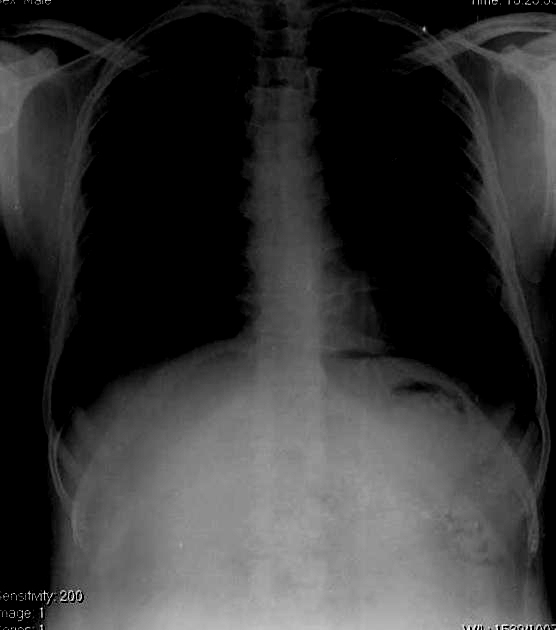

Cliche de face ASP

: Image radiologique de pancreatite chronique le

plus souvent sur ASP est image de calcification

parenchymateuse ou canalaire du pancreas . Parfois on en

voyait image de calcification vasculaire de artere splenique

. Ce sont des opacite multiforme , souvent nodulaire avec de densite eleve alonge

l,axe du pancreas

Image radiologique de

calcification d'une pancreatite chronique peut

en presence par hazard d'une cliche de face

pulmonaire PA . . A la region a travers L1 , L2 a

gauche on peut en voyant image des opacites calcifie

du pancreas de la maladie |